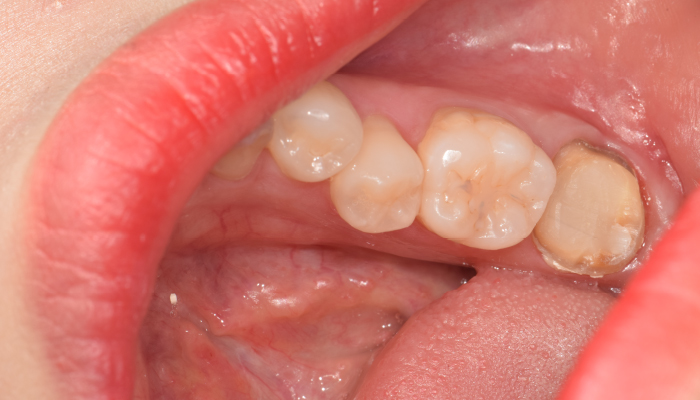

신경치료 전후 사례

• 치료 전

치료 후

• 치료전

치료후